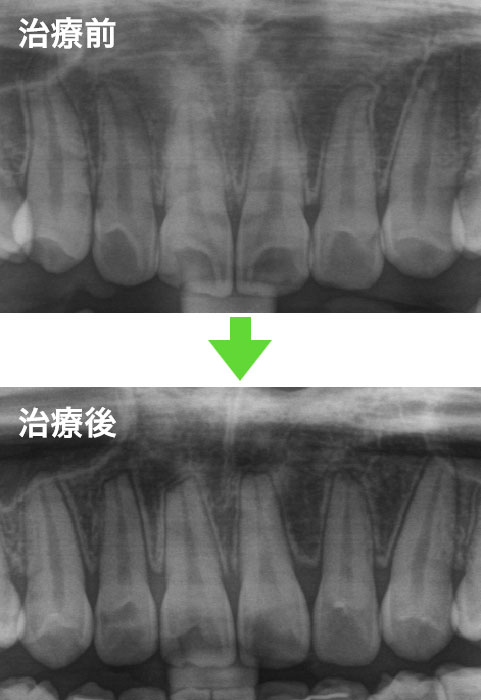

歯を動かすことにより、歯根が短くなることがあります(歯根吸収)。

研究では、矯正治療を受けた歯の90%に歯根吸収が起こると報告されています。多くの人は3mm以内で収まります。重度の歯根吸収は、1~5%の歯にしか見られません。

研究では、矯正治療を受けた歯の90%に歯根吸収が起こると報告されていますので、矯正治療における主な副作用と言えます。多くの人は3mm以内で収まります。重度の歯根吸収は、1~5%の歯に起こると報告されています*。もともと歯根の長さには個人差があり、歯根が短い人ほど将来的な予後は不利と言えますが、割合としては小さいです。特に歯根が短いと言える場合は診断時にご説明します。歯根吸収は、通常、歯を動かす治療が終わると止まります。